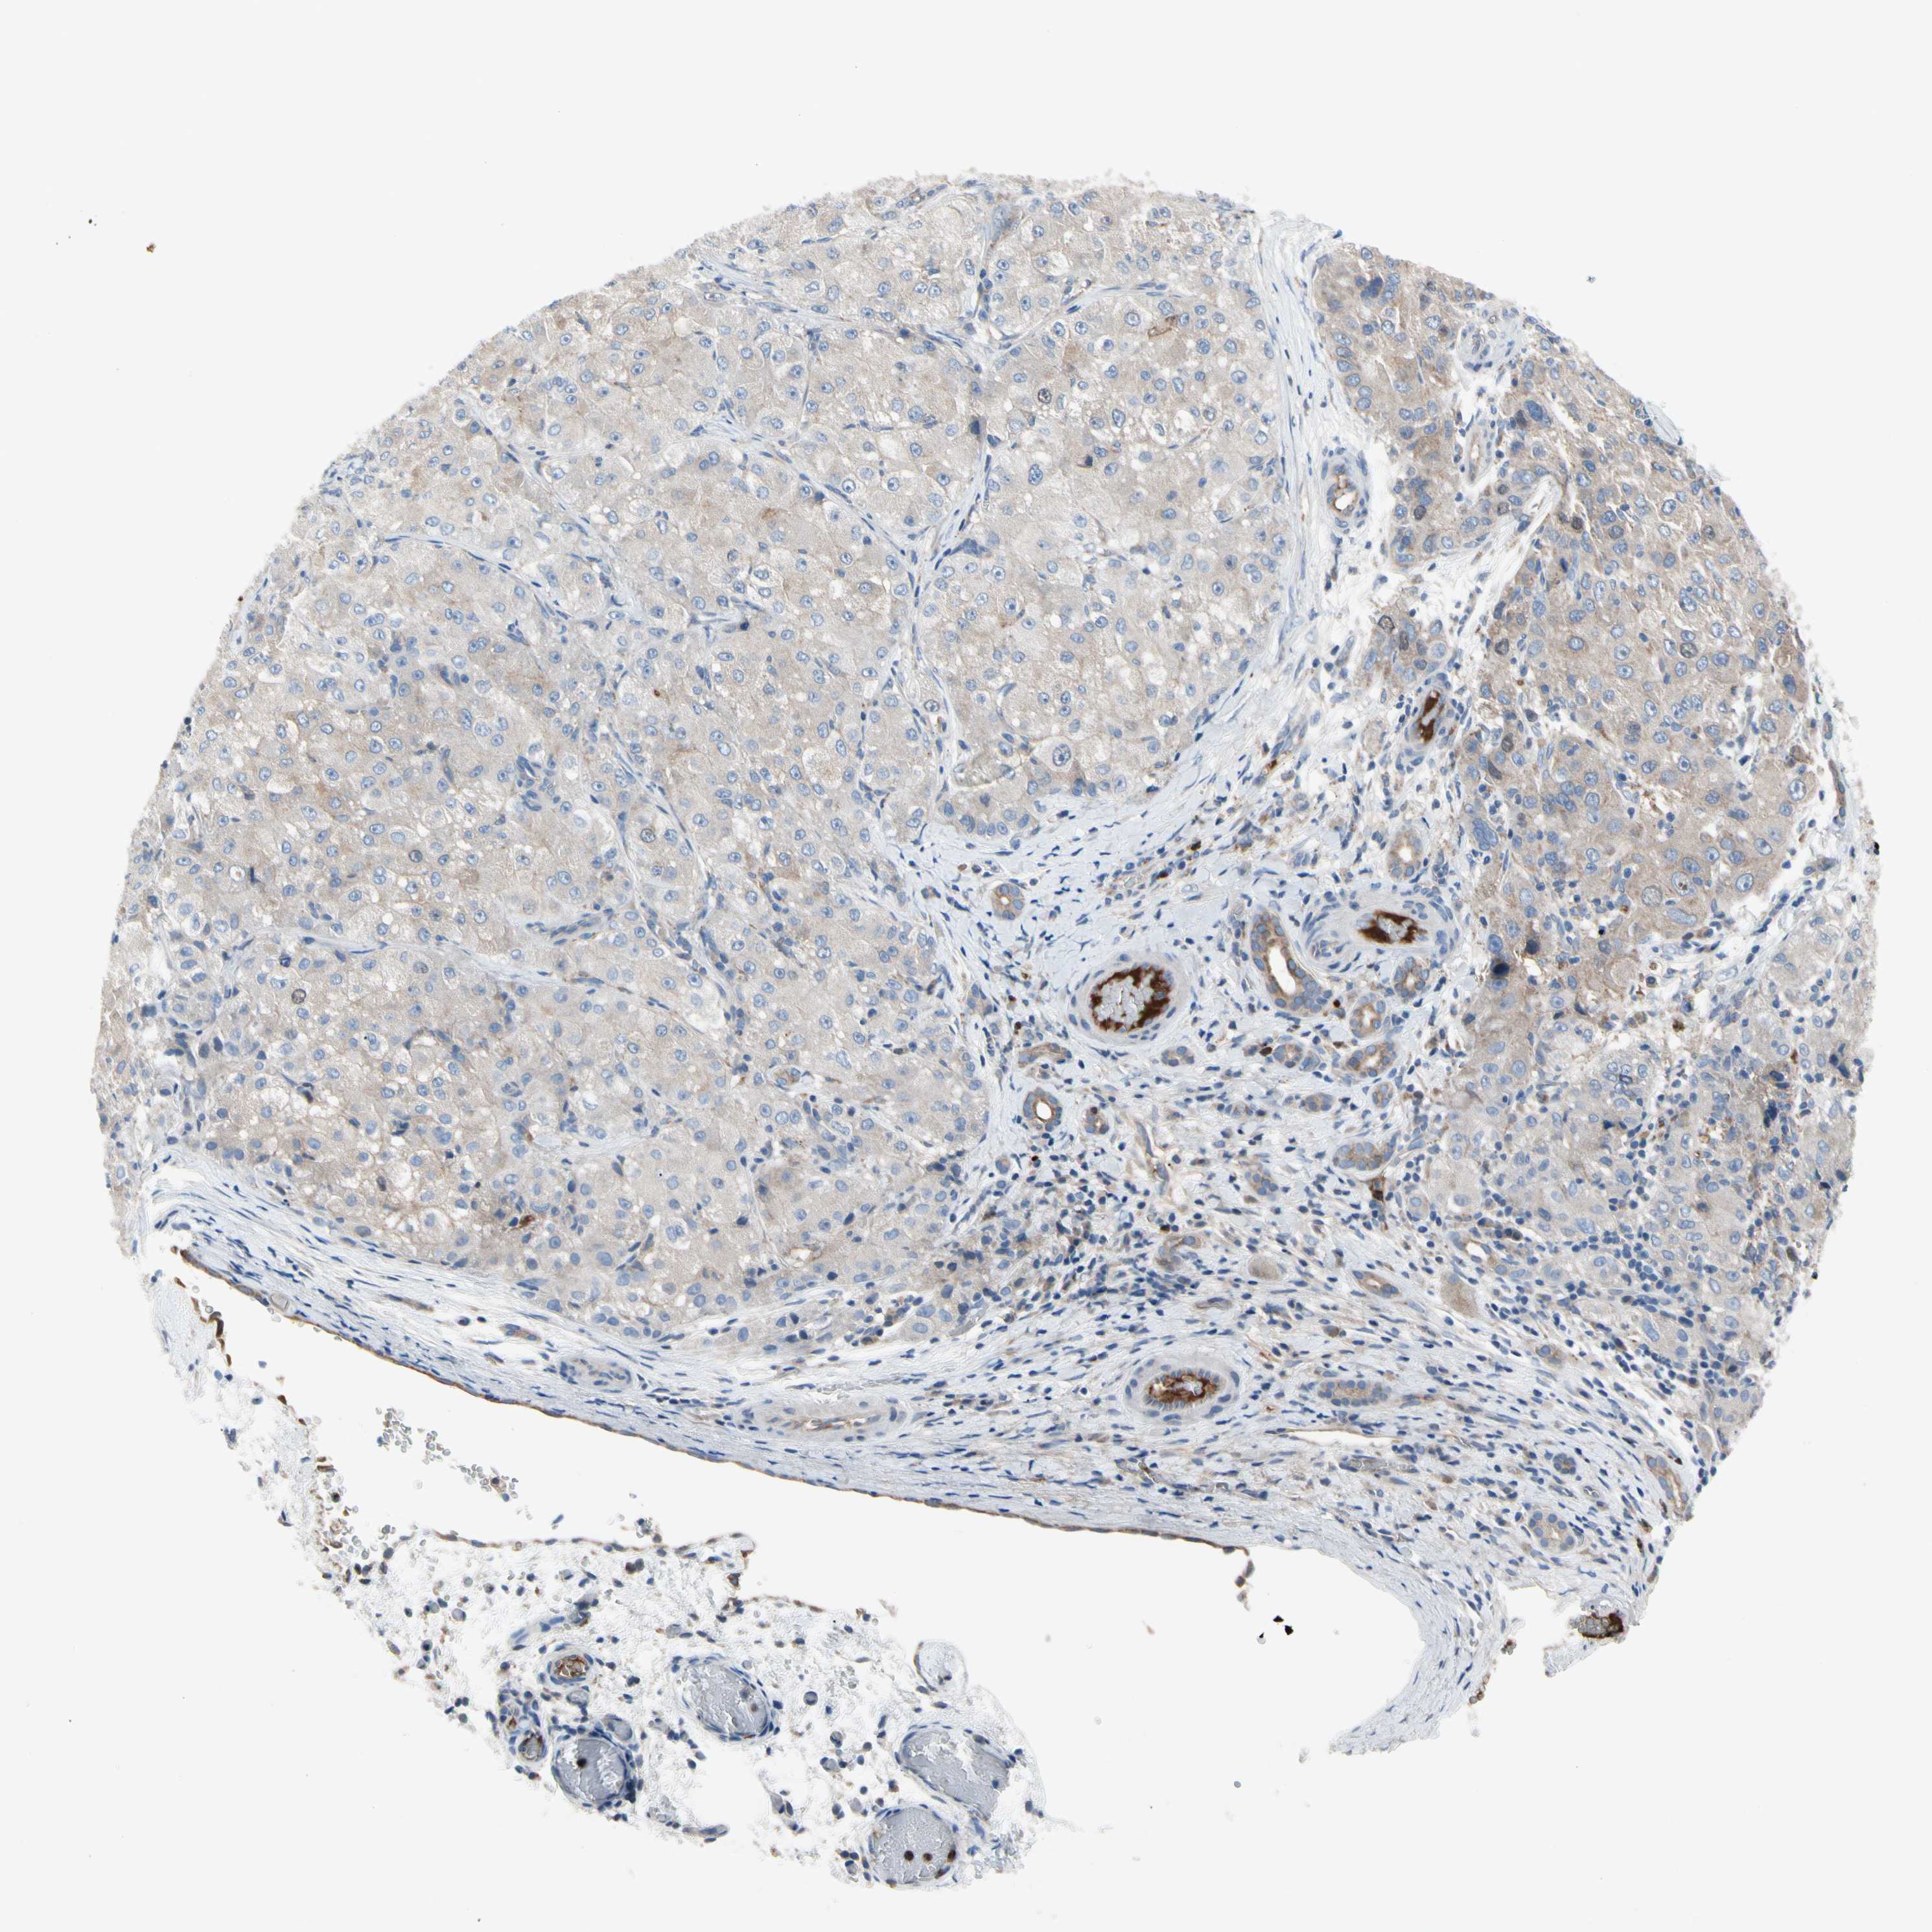

LIVER CANCER - Protein expressioni

A mouse-over function shows sample information and annotation data. Click on an image to view it in a full screen mode. Samples can be filtered based on level of antibody staining by selecting one or several of the following categories: high, medium, low and not detected. The assay and annotation is described here.

Note that samples used for immunohistochemistry by the Human Protein Atlas do not correspond to samples in the TCGA dataset.

Antibody stainingi

Antibody staining in the annotated cell types in the current human tissue is reported as not detected, low, medium, or high, based on conventional immunohistochemistry profiling in selected tissues. This score is based on the combination of the staining intensity and fraction of stained cells.

Each image is clickable and will lead to virtual microscopy that enables deeper exploration of all samples and also displays staining intensity scores, fraction scores and subcellular localization as well as patient and tissue information for each sample.

Antibody HPA008436

Staining

High

Medium

Low

Not detected

Intensity

Strong

Moderate

Weak

Negative

Quantity

>75%

75%-25%

<25%

None

Location

Nuclear

Cytoplasmic/membranous

Cytoplasmic/membranous,nuclear

Cholangiocarcinoma

Carcinoma, Hepatocellular, NOS